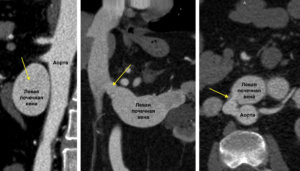

По данным МСКТ агиографии от 2020 обнаружено аорто-венозное сообщение (у здоровых людей такого не наблюдается) между аортой и левой почечной веной, веретенообразно расширенной до 9см!